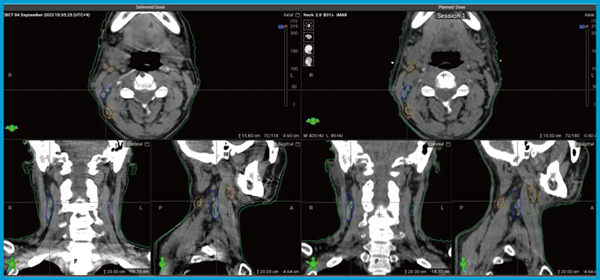

CTベースのonline-ARTは,CBCTで取得する画像の高精度化と全体的な治療時間の短縮が非常に重要である。ETHOS Therapyでは,現状CBCT撮像に約20秒かかり,速いモードに変えたとしても17秒程度を要するが,HyperSightでは,ガントリスピードが6RPMとなり,約6秒でCBCT撮像可能となった。今回,HyperSightの実際のCBCTをレビューしながら,期待される画質の向上や治療時間の短縮について評価した。

頭頸部癌におけるHyperSightを用いたCBCTの検証

まず,頭頸部癌における従来のCBCTの課題は,肩関節レベルのアーチファクト,嚥下のモーションアーチファクト,そして高吸収アーチファクトが挙げられる。これらの課題がHyperSightを用いるとどのように改善されるのかを検証した。肩の画像では,リングアーチファクトが出ていたが,少し改善されていた。次に喉頭の画像を見ると,参照した症例に動きがあったか不明だが,6秒で画像取得できれば嚥下によるモーションアーチファクトを抑えられる可能性が高い。顎の画像では,アーチファクト低減処理なしであるため,アーチファクトが完全にゼロにはならないが,一つ一つの構造物側の輪郭がしっかりと見えるという印象であった(図2)。

次に,HyperSightで可能になったメタルアーチファクトリダクション(MAR)処理の有無で画像を比較してみた。明らかに,MAR処理をした画像はメタルアーチファクトが改善されていた。

中咽頭癌の症例では,SIB法IMRTで小さなリンパ節を正確に狙いたい場合,画質が相当良くないと難しいが,HyperSightでは小さな血管やリンパ節が明瞭に描出されていた(図3)。この症例は,喉頭咽頭のレベルに多少モーションアーチファクトがあったが,リンパ節の描出までは影響していなかった。

図2 HyperSightによるCBCT(顎)

左:HyperSight 右:従来のCBCT

図3 HyperSightによるCBCT(中咽頭癌)

左:HyperSight 右:治療計画CT